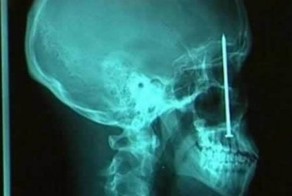

- Рентгеновский снимок, который шокируют Вас